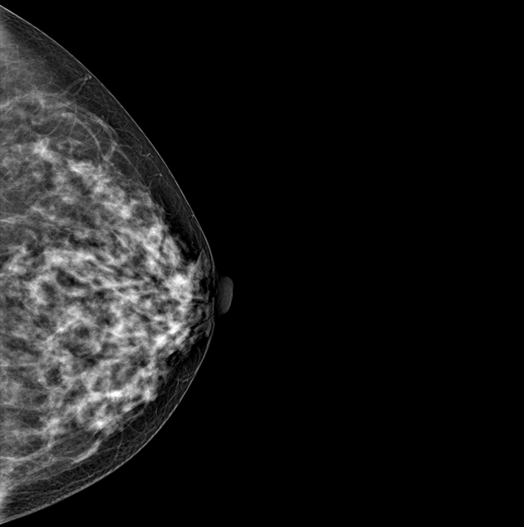

SYNTHESIZED 2D

HESTIA supports "Synthetic 2D" that generates 2D images only by tomography shooting without additional 2D shooting.